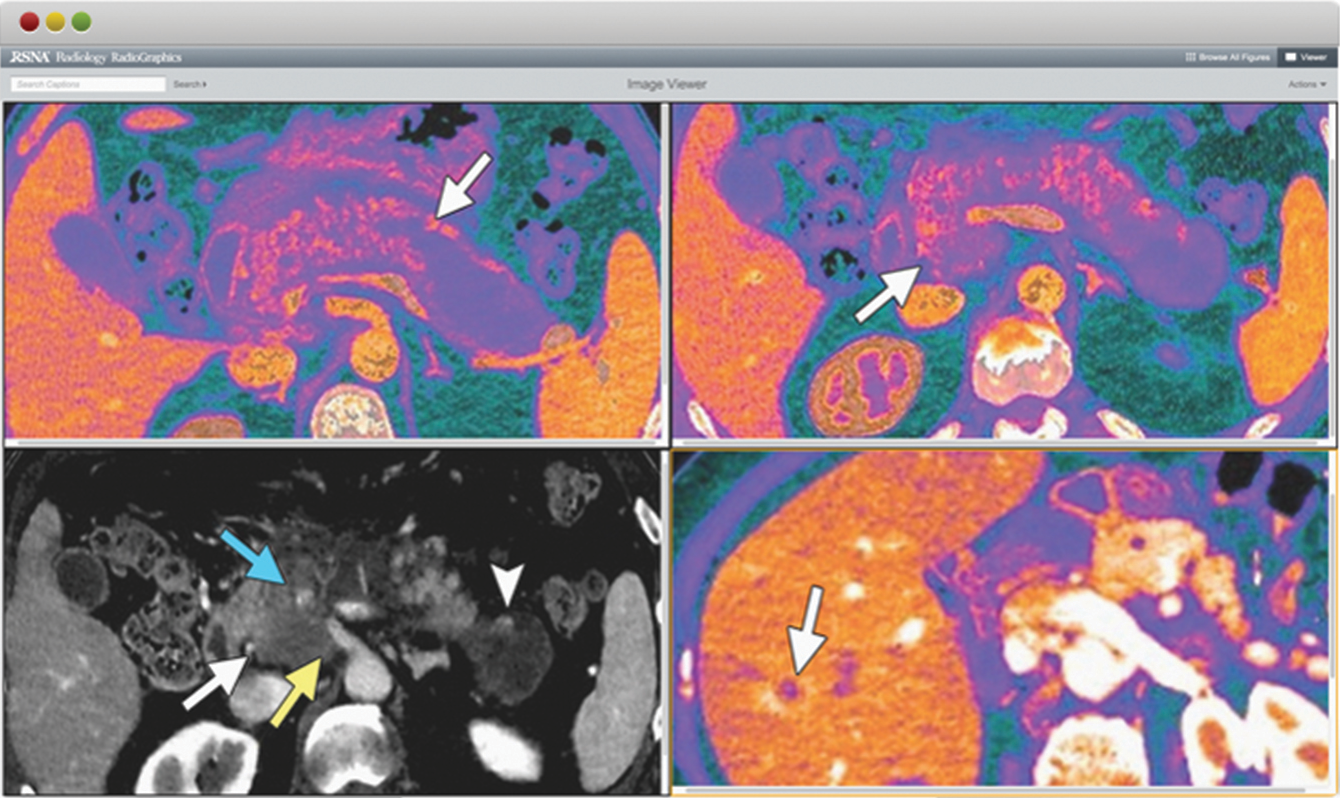

The RSNA Image Viewer, which debuted in June, gives users a rich new interface for viewing and comparing images. New capabilities include: comparing up to four images from the same article (two when using a tablet); zooming in and out of images or focusing on specific areas with the magnifier; and downloading images and captions to a PowerPoint deck to use for teaching or self-study. RSNA members can also save images as bookmarks in myRSNA® to access anytime. The tool is available for all articles in both journals.

The zoom function allows images to maintain their resolution upon magnification, so users can examine the type of subtle finding that might illustrate a mammographic study, for example.